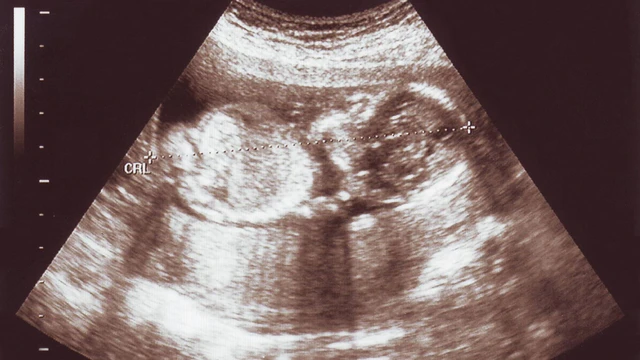

Thận ứ nước ở thai nhi là một trong những bất thường hệ tiết niệu thường được phát hiện qua siêu âm thai kỳ. Việc hiểu rõ tại sao thai nhi bị thận ứ nước, cách chẩn đoán và chăm sóc phù hợp sẽ giúp gia đình chủ động phối hợp với bác sĩ, đảm bảo an toàn cho trẻ ngay từ giai đoạn đầu đời.